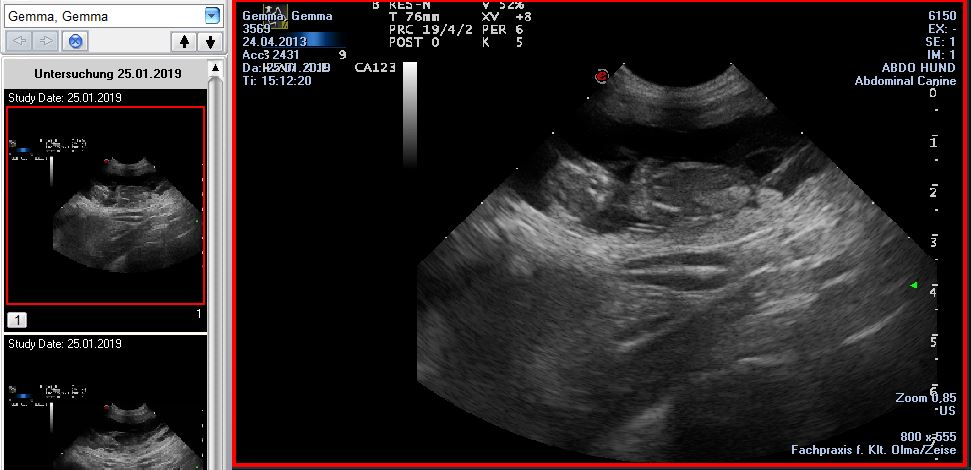

25.01.2019

Ein weiteres Ereignis steht an!

Wir erwarten Ende Februar Welpen von Twinkle Newman und unserer Gemma.

Und hier grüßt auch gleich die Nr. 1 :)